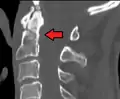

Type 2 dens fracture